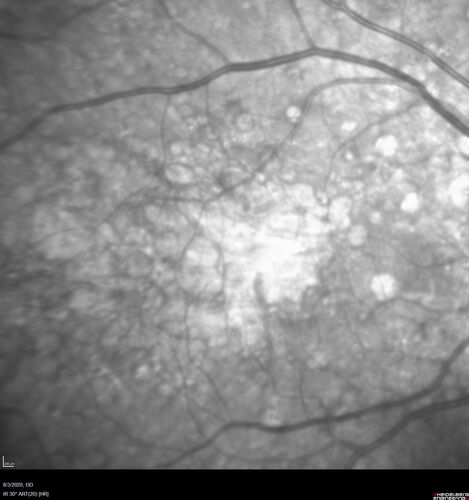

Age-related macular degeneration - Geographic Atrophy - Intermittent CME left eye from CRVO, Anemia, Diabetes

79 year old female - 3 years post CRVO in the left eye (20/32 VA) with intermittent CME.  Left eye is the better eye.  Vision is stable since 2 years ago

PMHx: Type II DM x 20 years, Chronic Anemia, Hyperlipidemia

VA 20/200 OD, 20/50 OS (usually 20/40)